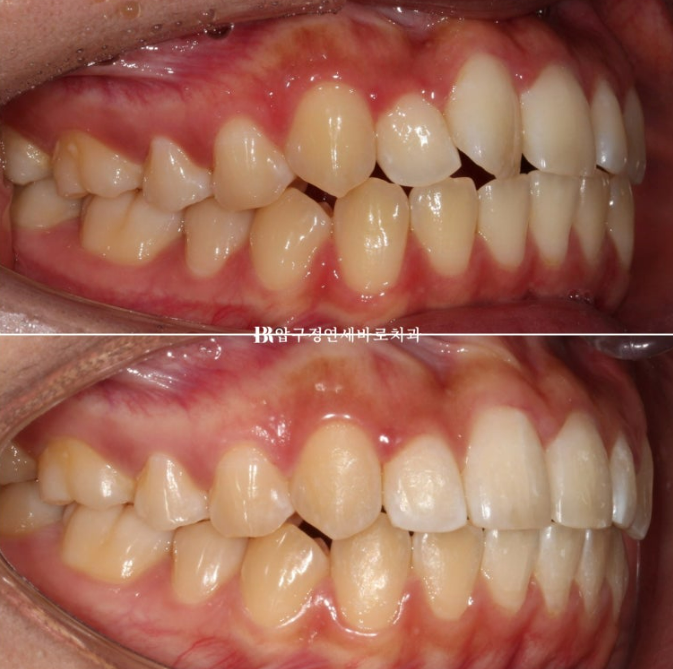

전 후 비교 보겠습니다.

토탈 치료기간은 6개월입니다.

23.12~24.06

심해보이는 덧니도 적절하게 치료한다면 의외로 짧고 간단하게 교정이 마무리가 됩니다.